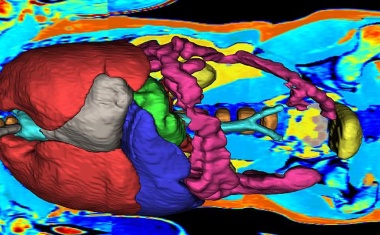

Ein Forschungsteam der Universität Würzburg hat ein KI-Modell entwickelt, das dreidimensionale Bilder in der Medizin besser interpretiert als andere Modelle.